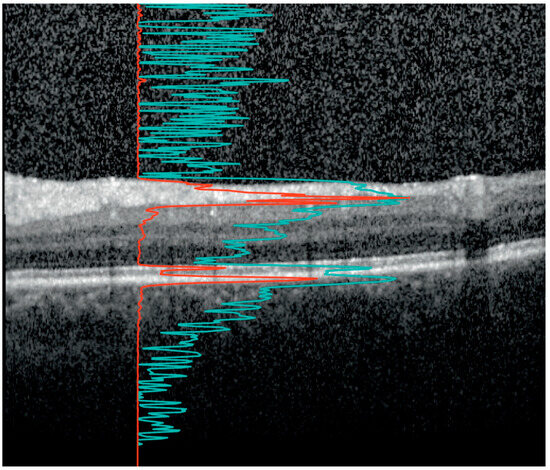

2.2. Retinal Layer Thickness and Vitreous Haze Measurements

- Montesano, G.; Way, C.M.; Ometto, G.; Ibrahim, H.; Jones, P.R.; Carmichael, R.; Liu, X.; Aslam, T.; Keane, P.A.; Crabb, D.P.; et al. Optimizing OCT acquisition parameters for assessments of vitreous haze for application in uveitis. Sci. Rep. 2018, 8, 1648. [Google Scholar] [CrossRef]

- Liu, X.; Kale, A.U.; Ometto, G.; Montesano, G.; Sitch, A.J.; Capewell, N.; Radovanovic, C.; Bucknall, N.; Beare, N.A.V.; Moore, D.J.; et al. OCT Assisted Quantification of Vitreous Inflammation in Uveitis. Transl. Vis. Sci. Technol. 2022, 11, 3. [Google Scholar] [CrossRef]

- Coric, D.; Ometto, G.; Montesano, G.; Keane, P.A.; Balk, L.J.; Uitdehaag, B.M.J.; Petzold, A.; Crabb, D.P.; Denniston, A.K. Objective quantification of vitreous haze on optical coherence tomography scans: No evidence for relationship between uveitis and inflammation in multiple sclerosis. Eur. J. Neurol. 2020, 27, 144-e3. [Google Scholar] [CrossRef] [PubMed]

- Keane, P.A.; Balaskas, K.; Sim, D.A.; Aman, K.; Denniston, A.K.; Aslam, T.; Equator Study Group. Automated Analysis of Vitreous Inflammation Using Spectral-Domain Optical Coherence Tomography. Transl. Vis. Sci. Technol. 2015, 4, 4. [Google Scholar] [CrossRef]